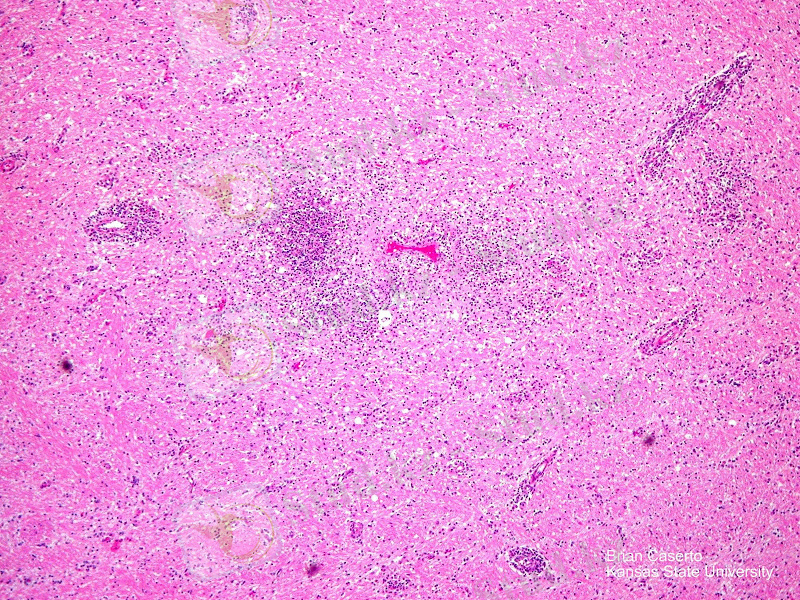

Листериозға жұлынның, ми жүйкелерінің ( 5, 7, 9 немесе 12 жұптары), мидың белгілі бір бөлектерінің ҚАБЫНУЫ тән. Сопақша ми мен көпір зілді, ортаңғы ми мен жұлынның мойын бөлімі біршама бәсеңдеу қабынады, ал мишық пен көру дөңесінің қабынуы шамалы болады. Жұмсақ қабық өте зiлдi қабынып, лимфоциттермен, гистиоциттермен, бірен-саран нейтрофильдермен кеуленеді. [2]

Микроабсцесс белгілерімен жіті іріңді байқаймыз. [3]

Энцефалит: А. Қозы миы Б. Ірі қара малдың сопақша миы

Ми талшығы: А. Периваскулярлы инфильтрацияның майда ошақтары. Тамырлар қабынған торшаларға толып және қоршалып тұр.

Б. Нейрофилдерден (сандары әртүрлі макрофаг пен лимфоциттер) тұратын периваскулярлы қабынған торшалар.

Мида лейкоциттер мен гистиоциттердің шоғырланған, жайылған және қан тамырларын тікелей қоршаған шоғырлары байқалады. Қабыну процесі ми затындағы лейкоциттердің шоғырларымен басталады да, кейін микроглия көбейіп, гистиоциттер пайда болып полиморфты сипат алады. [2]